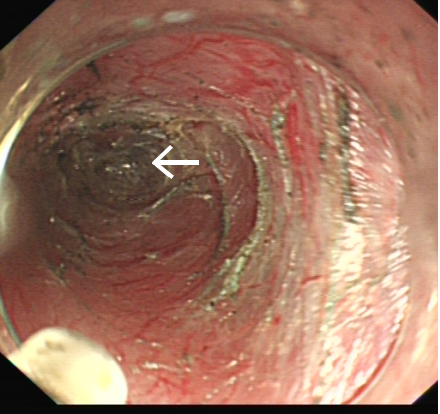

此時(shí)已經(jīng)過(guò)去2周,魚(yú)刺刺入的部位已完全愈合,內(nèi)鏡下見(jiàn)到的食管黏膜已十分光滑,未留下任何蛛絲馬跡。但魚(yú)骨在體內(nèi)停留的時(shí)間越長(zhǎng),導(dǎo)致消化道穿孔、大動(dòng)脈破裂出血、難以控制的縱隔和胸腔感染、頸部膿腫致呼吸困難等嚴(yán)重并發(fā)癥的機(jī)率越大,這不僅時(shí)刻威脅著患者的生命安全,也給患者帶來(lái)巨大的心理負(fù)擔(dān)。

但手術(shù)遠(yuǎn)比想像中更為困難,由于解剖結(jié)構(gòu)的因素,內(nèi)鏡在高位食管建立黏膜下隧道本來(lái)就有很高難度,還要在狹窄的隧道內(nèi)完成超聲內(nèi)鏡檢查,既不能發(fā)生食管穿孔,又要準(zhǔn)確定位魚(yú)刺,挑戰(zhàn)十分嚴(yán)峻。內(nèi)鏡中心多位醫(yī)生輪番上陣,在護(hù)理團(tuán)隊(duì)嫻熟配合下,經(jīng)過(guò)長(zhǎng)達(dá)數(shù)小時(shí)的地毯式搜尋,終于發(fā)現(xiàn)魚(yú)刺的蹤跡。鑒于已發(fā)生過(guò)取出過(guò)程夾斷魚(yú)刺的情況,為保證魚(yú)刺完整,在反復(fù)超聲探查判斷術(shù)中引發(fā)魚(yú)刺穿破食管的可能性不大后,醫(yī)生們采用了一種新辦法:在魚(yú)刺遠(yuǎn)端的食管黏膜再切開(kāi)一道深度接近肌層的小切口,然后自魚(yú)刺近端建好的黏膜下隧道再次進(jìn)鏡,終于將這根長(zhǎng)約2.4cm的“流浪”魚(yú)刺完整地從遠(yuǎn)端的切口里“推趕”了出去。

此次手術(shù)是我院首次采用隧道內(nèi)鏡技術(shù)完成食管黏膜下異物探查,取出魚(yú)刺的操作在黏膜下層完成,除了近遠(yuǎn)端兩個(gè)小切口,隧道表面的黏膜和底部的肌層均保持完整,術(shù)后房大姐恢復(fù)迅速,隔天就出院回家,恢復(fù)正常飲食后無(wú)任何不適,全家懸著的心終于落了地。這也是我院首次在消化內(nèi)鏡中心手術(shù)間完成氣管插管全麻,數(shù)小時(shí)的手術(shù)過(guò)程麻醉深度適宜,患者生命征平穩(wěn);超聲科全程在場(chǎng)提供超聲技術(shù)支持,為手術(shù)的成功提供了有力保障。據(jù)文獻(xiàn)檢索,目前國(guó)內(nèi)外尚無(wú)采用近遠(yuǎn)端雙切口順行推送取出食管黏膜下異物的報(bào)道。